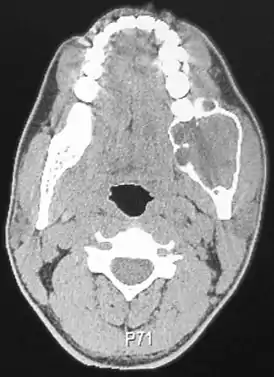

![]() Компьютерная томография амелобластомы | |

Независимо от происхождения адамантинома (1,0 % всех кистозных образований челюстей, возникают у лиц молодого и среднего возраста, в 80,0 — 92,0 % случаев локализуется в нижней челюсти, в зоне угла, ветви и дистальных отделов тела челюсти — участки моляров и премоляров) эмали не производит.

Кистозная форма представлена значительным количеством пустот мультицикличного характера, разделенных перегородками из костной ткани. Изредка кистозная форма адамантиномы может быть однокамерной, заключая в себе непрорезанный зуб, напоминая фолликулярную кисту; однокамерность при этом обусловлена слиянием кистозных полостей. Челюсть в месте патологии деформируется, лицо становится асимметричным в дистальных отделах. Периостальная реакция, как правило, отсутствует, зубы не смещены. Прозрачность тени многокамерной опухоли неоднородная, максимальная — в центре, иногда наблюдаются воспалительные осложнения в одной из кист, эрозии корней, в отличие от остеобластокластомы, не наблюдается.

При солидной форме визуализируется округлой или овальной формы одиночное просветление преимущественно в области угла нижней челюсти. Дифференцировать солидные адамантиномы следует исходя из эпителиальных кист и дрибносотистых образований, в частности остеобластокластомы.